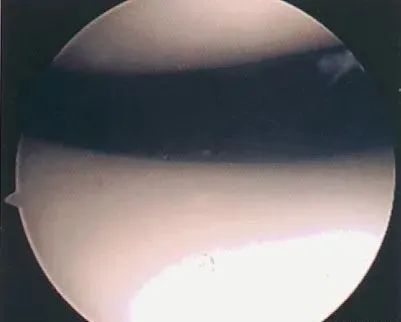

• 关节镜:是髌骨软化症确诊与治疗的有效手段之一,可以在镜下直接观察软骨面的变化,但不能够观察到软骨下骨的变化

关节镜下可将髌骨软化分为5级:

0级:正常关节软骨

Ⅰ级:关节软骨失去珍珠样外观而变得较暗淡,局部软化,肿胀区或纤毛化区的直径<0.5cm。

Ⅱ级:关节软骨软化区内出现毛刷状或纤毛化改变,深达1~2mm,直径≤1.3cm。

Ⅲ级:软骨的毛刷状或纤毛化改变达关节软骨厚度一半以上,直径>1.3cm,关节软骨表面类似蟹肉样改变,表面有多发软骨碎片附着其下的软骨。

Ⅳ级:关节软骨全层受侵,软骨下骨暴露,表现为进展期髌股关节炎。